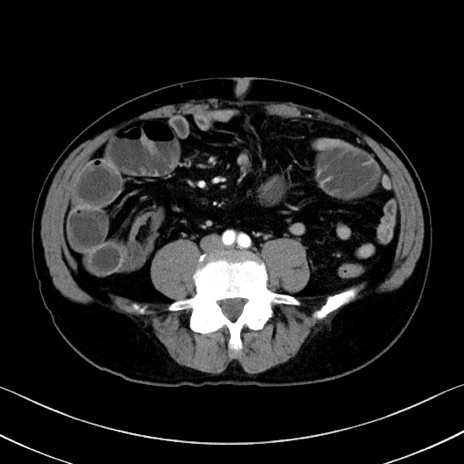

症例35(横断像)

冠状断像

【症例】70歳代 男性

【主訴】腹部膨満、嘔吐

【現病歴】昨日より腹部膨満感出現。本日増悪し、仙痛出現。嘔吐あり、受診。

【既往歴】糖尿病、胆摘後

【身体所見】BP 149/80mmHg、HR 74/min、BT 35.9℃、腹部:膨満、軟、圧痛なし。腸雑音減弱あり。上腹部正中切開瘢痕あり。

【データ】WBC 13500、CRP 1.72